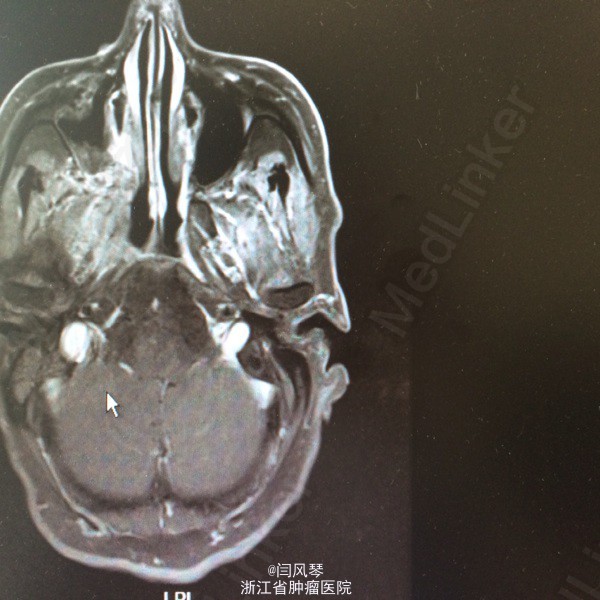

患者男,58岁,鼻咽癌放疗近2年,因鼻咽部复发于2015.6.12-2015.8.25于当地医院行TP方案化疗4周期,现化疗后1月余,诉右耳听力下降,右侧口角周围皮肤麻木感,为进一步诊治就诊于我院,门诊拟“鼻咽恶性肿瘤复发”收治。

一般可,生命体征平稳,鼻咽右侧壁及顶壁见新生物,双颈部未及明显肿大淋巴结。

诊断:鼻咽恶性肿瘤复发。治疗:复发灶局部放疗

讨论:患者鼻咽部放疗后复发,行4周期化疗后,肿瘤残留较明显,有局部放疗指征,但患者首程放疗后近两年,时间较短,再程放疗易引起鼻咽部溃疡大出血、放射性脑病、放射性神经损伤灯较严重的并发症,需积极预防及治疗